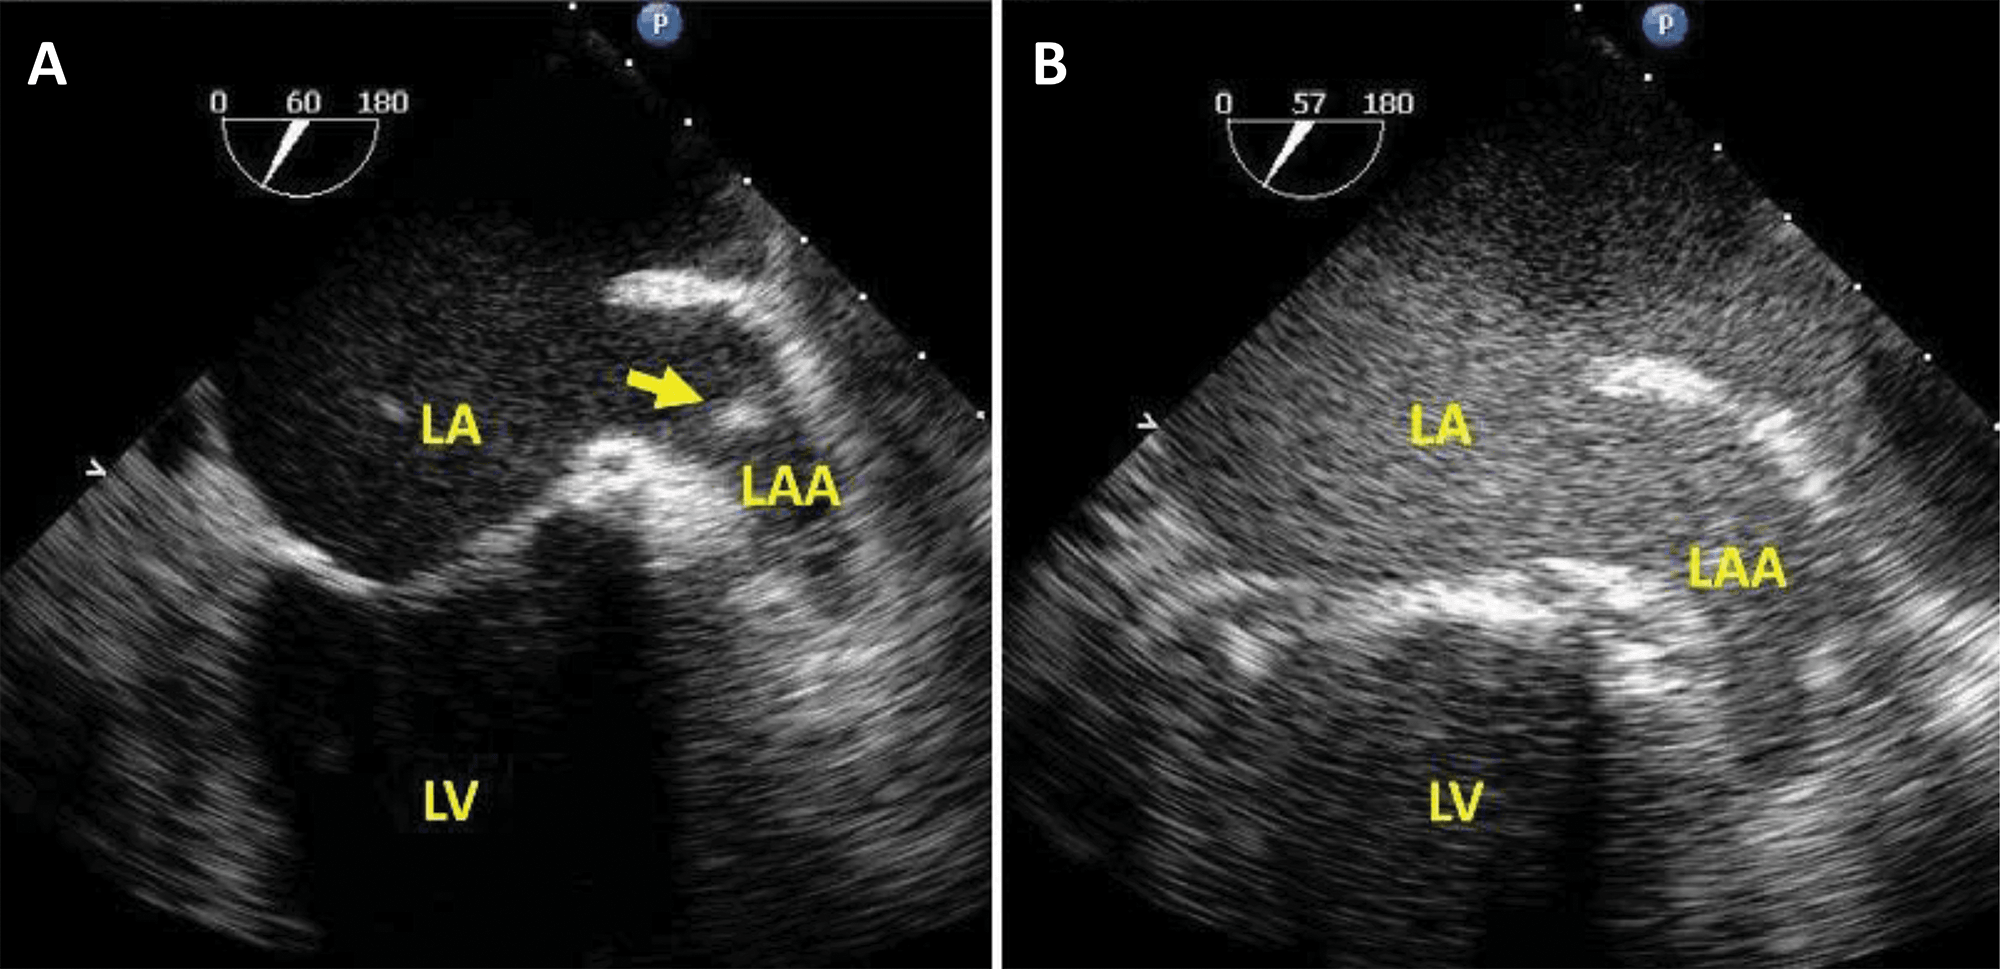

Fig. 6.Transoesophageal echocardiography in a patient with a Watchman left atrial appendage (LAA) closure device. Microbubble-enhanced ultrasound was used in order to detect a suspected residual leak around the occluder. On non-enhanced multiplane and live 3D images (A) a gap is visible (red arrows) between the rim of the device and the LAA. Because of shadowing, the sealing of the LAA cannot be verified. By adding intravenous contrast (B) and using harmonic imaging with a mechanical index of 0.2, contrast is seen in the LAA, surrounding the device (yellow arrows), demonstrating incomplete sealing of the LAA. Source: personal collection.